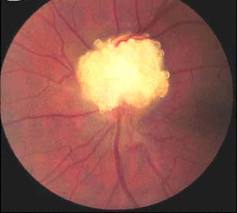

Constituyen una importante fuente de pérdida de visión. Se componen de concreciones de calcio, aminoácidos y ácidos nucleicos, mucopolisacáridos y, a veces de hierro dentro del nervio óptico.

A veces se asocian con otras enfermedades oculares, como estrías angioides, retinitis pigmentosa, y glaucoma de ángulo abierto, pero lo normal es encontrarlos de manera casual. Puede ser congénita. Se hallan en un 0,2% a 0,3% de los caucásicos y asiáticos, pero rara vez en pacientes negros.

En un análisis retrospectivo de 103 ojos completado por Grippo et al, las drusas visibles presentan pérdida de campo visual mucho máyor que aquellos con drusas enterradas.